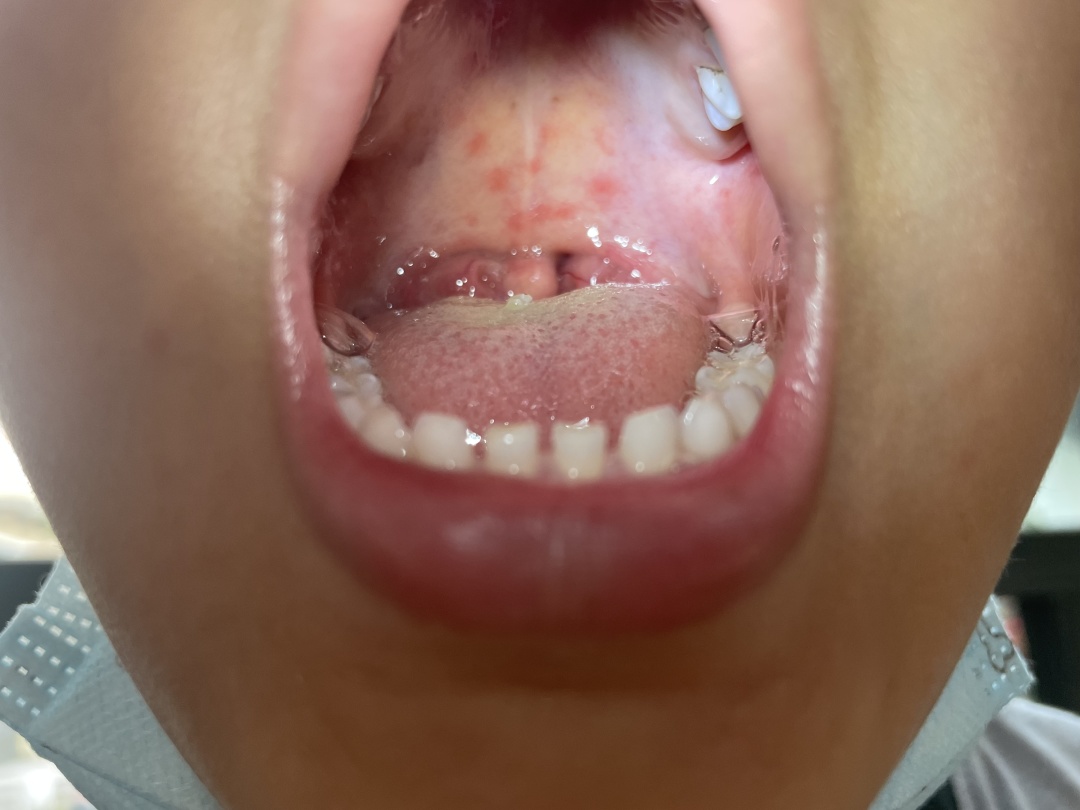

疱疹性咽峡炎是由肠道病毒引起的以急性发热和咽峡部疱疹溃疡为特征的

才上几天学,就从学校传染到了疱疹性咽峡炎,满嘴水泡,不能吃不能喝

宝妈分享的孩子疱疹性咽颊炎从头到尾的咽部改变,终于熬出头了,除了

疱疹性咽峡炎主要的症状有突发高热,咽部见小红点,随后成小水泡,最后

以上,可因咽痛及口腔疱疹疼痛明显而出现流口水,拒食,呕吐,头痛等症状